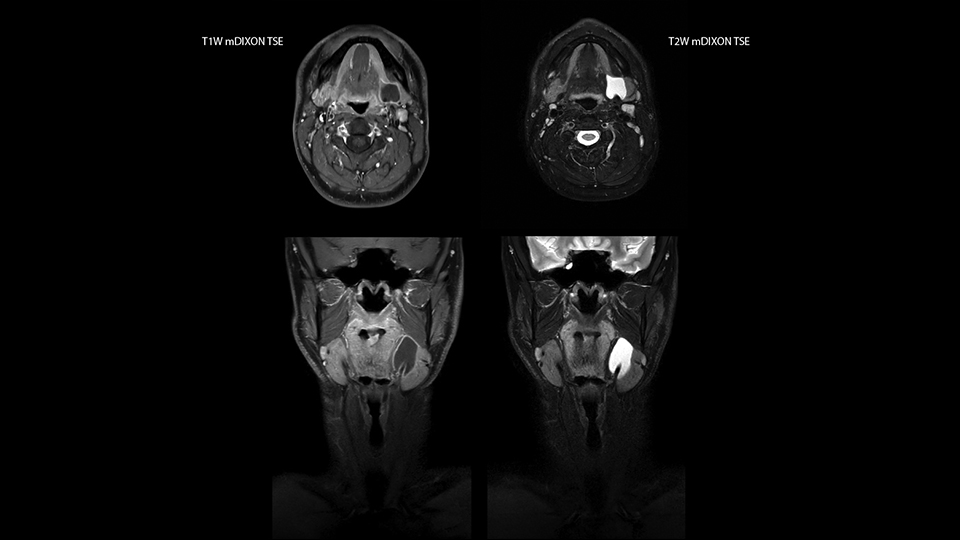

mDIXON TSE fat suppression helps DMG reduce repeats and supports diagnostic confidence

“Our DMG Lisle location includes a cancer center, so soft tissue neck scans, brachial plexus scans, and prostate scans are common. For these exams, mDIXON TSE provides excellent images with and without fat suppression all while helping us reduce repeats and work more efficiently,” Mr. Duffy says.

“With the 2-echo Philips mDIXON TSE the timing is short and the fatsat is very robust. The biggest thing is that you know your fat suppression will be good, even in thin patients or large patients that are off-center,” Mr. Sybesma says.

“Since we work in fixed time slots, not having to repeat scans is key for us,” Mr. Duffy adds. “With mDIXON TSE we get high quality results the first time – unless of course the patient absolutely jumps off the table. For us, that’s significant, because just a single repeat scan could put us behind schedule.

“mDIXON TSE raises our diagnostic confidence with its homogeneous

fat suppression. Neck exams and rheumatology patients are two examples where mDIXON TSE is especially useful,” Dr. Kaakaji says. “For us it’s also an efficiency boost in exams where we need pre and post T1-weighted images with great fat suppression.”

“mDIXON TSE raises our diagnostic confidence with its homogeneous fat suppression”